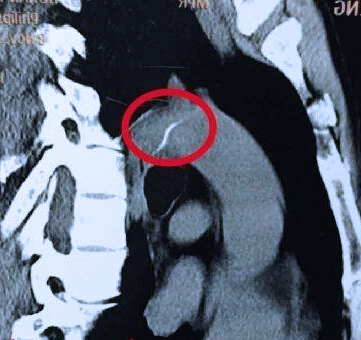

还有就是喉镜、胃镜一路检查下来也没发现鱼刺,但自己感觉总是有的这种情况,这样的话可能就要行具体部位的CT扫描了,可能是鱼刺扎进肉里面去了,喉镜胃镜这些检查根本发现不了,如果是这种鱼刺比上述就更麻烦一点了,同样需要评估位置和风险,可能需要行手术切开取出。